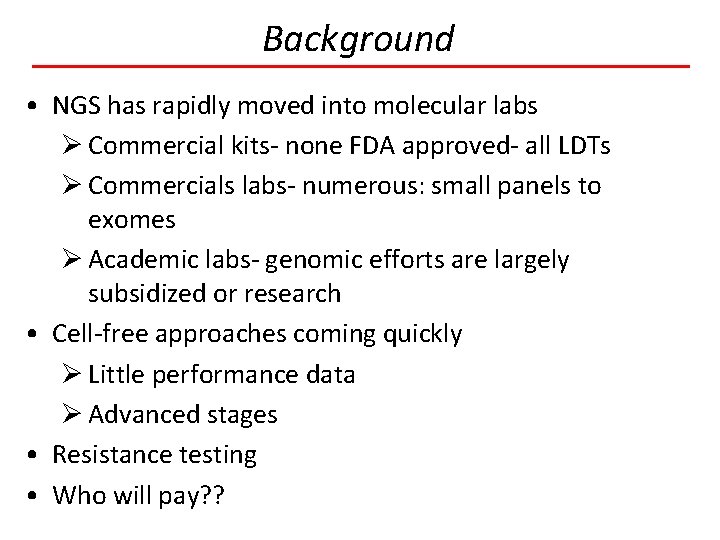

Background • NGS has rapidly moved into molecular labs Ø Commercial kits- none FDA approved- all LDTs Ø Commercials labs- numerous: small panels to exomes Ø Academic labs- genomic efforts are largely subsidized or research • Cell-free approaches coming quickly Ø Little performance data Ø Advanced stages • Resistance testing • Who will pay? ?